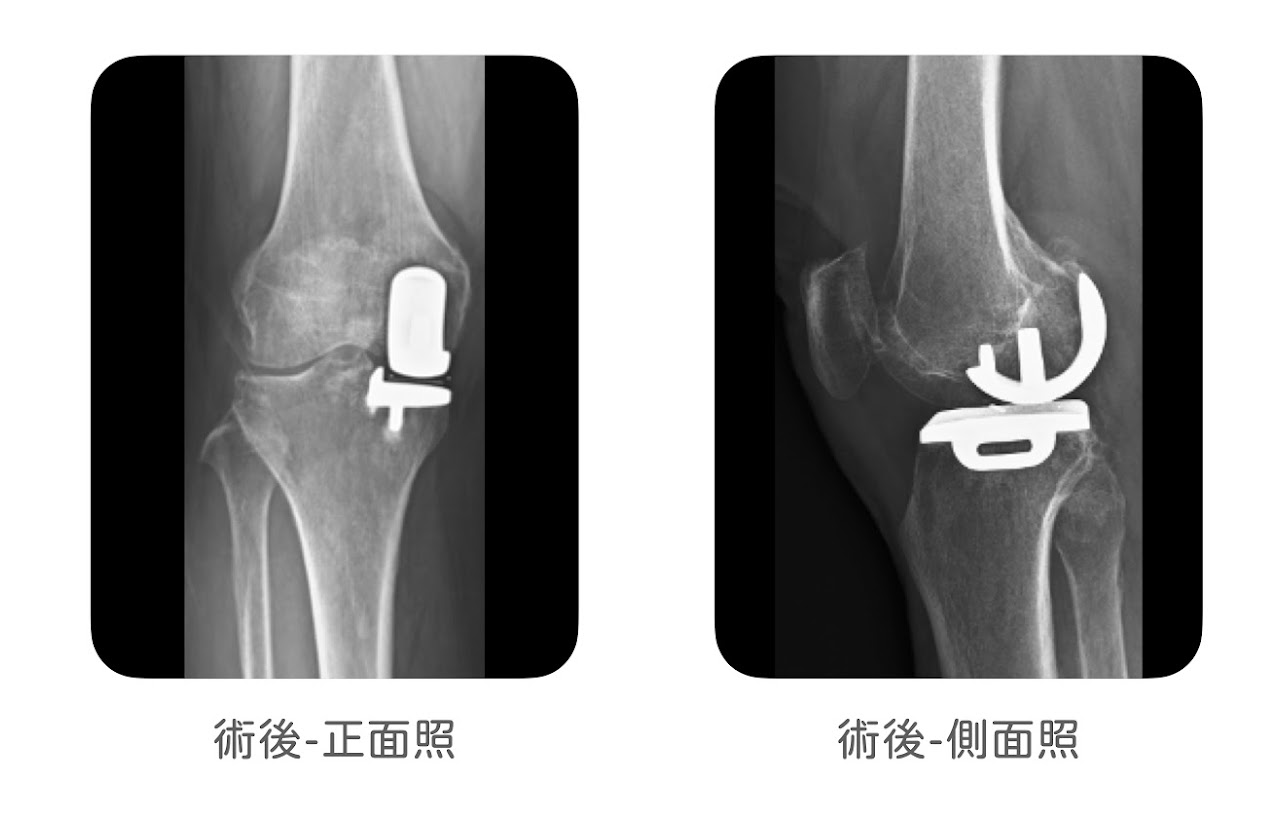

像是原本有厲害的 O 型腿合併內側關節炎(圖1),又或者是明顯的X型腿合併髕骨股骨關節脫臼(圖2),通常就不是部分人工關節置換手術適合處理的情況,所以部分人工膝關節置換手術,手術前需要確認角度沒有太大的偏差。

(圖2)